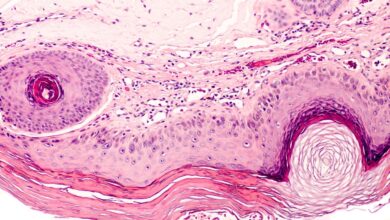

MỘT SỐ ĐIỀU CẦN BIẾT VỀ BỆNH ẤU TRÙNG DI CHUYỂN Ở DA

Bs.CKII. Đinh Thị Ái Liên 1. Đại cương: Bệnh ấu trùng di chuyển ở da có các tổn…